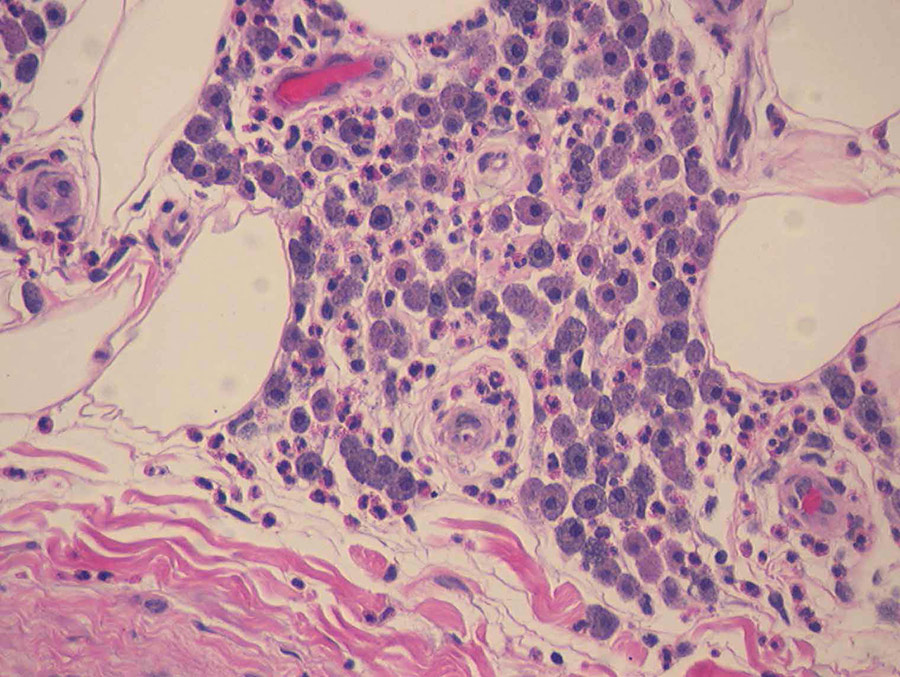

纽曼研究兴趣还伸展到诊断各种动物的胰岛素疾病上,犬巢病难以诊断,原因是缺乏高度具体敏感测试,尽管在她生涯中已经实现这一点。Pancriatis是最常见的狗排尿孔病之一 — — 也是发病和死亡的重要原因之一。狗肠炎分类系统上次更新于1992年,内含封膜炎类型定义模糊慢性胰炎是一种慢性炎,会影响周围组织并可能永久损害导致纤维化(组织萎缩)的脉冲急性胰炎是一种急性炎,引起点细胞死亡和消化酶渗入周围腹部脂肪,并产生配方化(烟雾编组),这是一种特征历史变换后者通常还伴生腹痛

少数研究报告狗脉炎骨折,直到纽曼哨点工作评价大量狗与此条件相关联的炎症局部化、纤维化和死死Newman解析狗死后研究中这些前未探索因素,通过她的研究 疾病进程正得到更好的特征化 提高胰岛炎诊断精度

测试血清标记敏感度诊断犬膜炎 Newman评估了狗上千封泛组织样本各种诊断测试测试类似免疫性测试以及血清amylase和lipse水平测试,自这些开拓性研究以来,警犬泛嘴免疫测试被兽医更广泛地使用,因为在诊断犬内胰腺炎时敏感度和特性提高PCLI还可用于泛洲损耗生物标志并被纳入全球泛洲炎测量测试评估多警犬泛证样本后,血清参考范围计算出来,测试在线提供,作为警犬使用血液样本诊断的有用辅助工具

病理损伤随机分布于狗肺炎中,单生素诊断难反之,针头求美结果记录不足Newman发现非入侵式FNA泛采样生成高质量细胞样本,并允许分析诊断FNA避免对ancreas和/或开发更多复杂问题造成重大损害稳定CPLI水平反映了这一点此项技术改进狗肠炎诊断并预防更强健生物检验程序造成的复杂或相关伤害